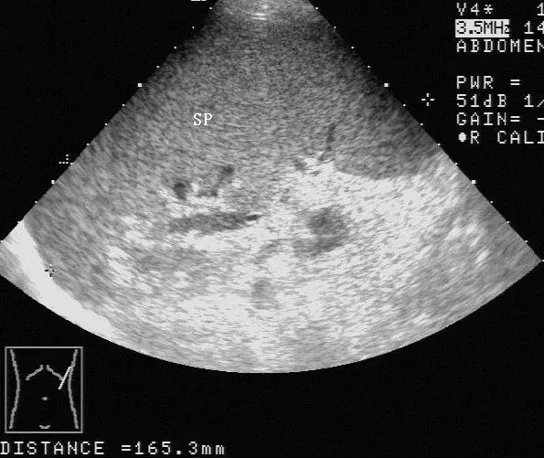

灰阶超声,脾肿大,显示肿大的脾脏(SP),内部回声均匀,长径为165mm。

SP:脾脏     SV:脾静脉。